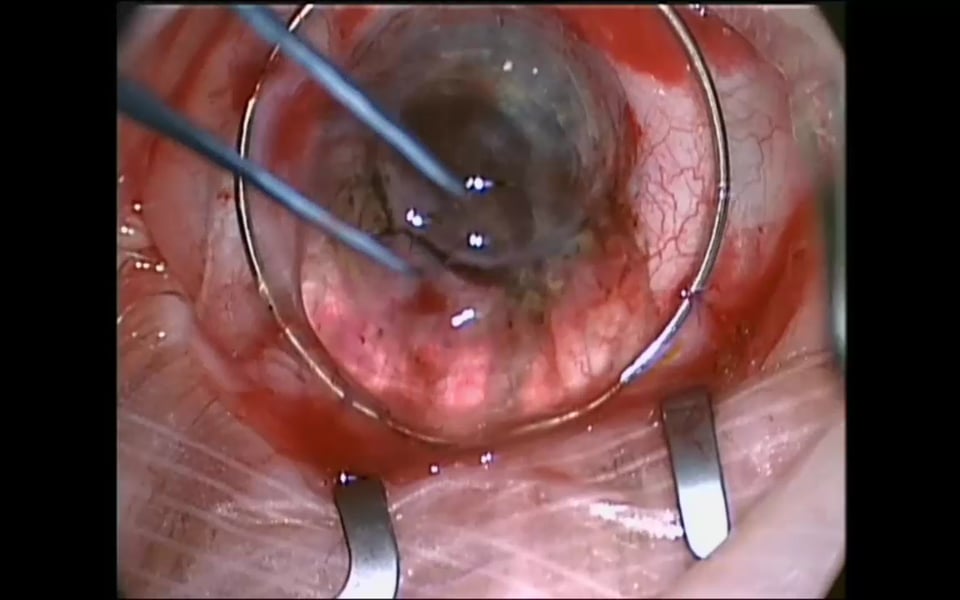

Advances in Ophthalmology - Corneal Transplantation, Cataract Surgery, Glaucoma Surgery & Vitreolysis Graham Lee 4081 Views